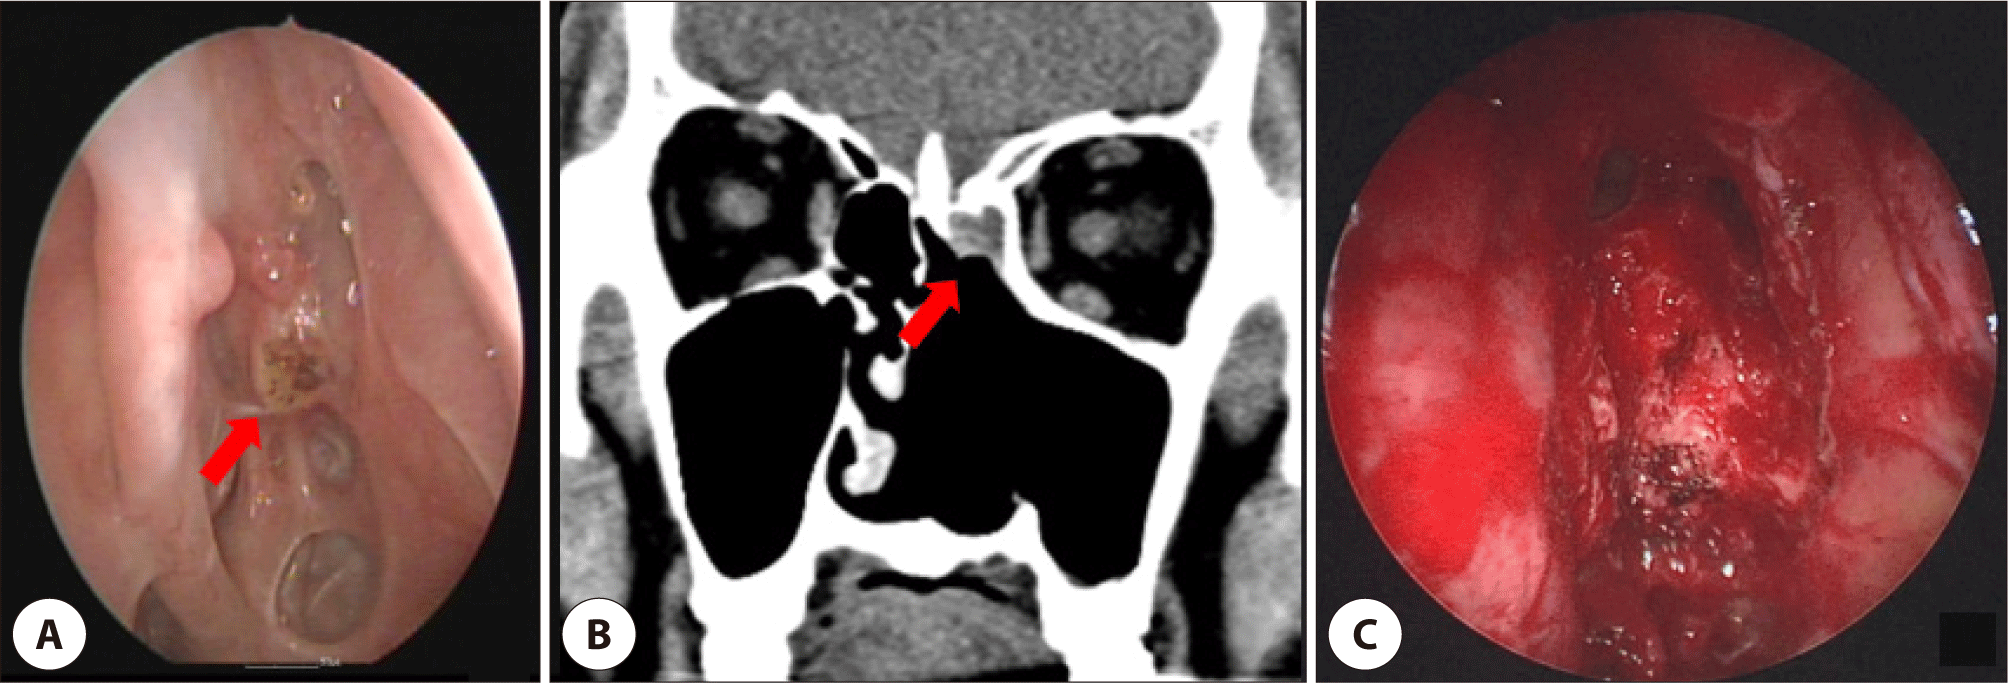

During follow-up, a 0.9 cm bleeding mass of left inferior turbinate was detected and diagnosed as SCC (Fig. 3A). On CT, a soft tissue mass of about 1.0×1.0 cm with irregular margins was detected. MRI revealed a slightly enhanced mass in the left inferior turbinate. Endoscopic left partial inferior turbinectomy was performed (Fig. 3B). Pathology revealed well-differentiated, minimally invasive SCC (invasion depth 0.2 mm) without lymphovascular or perineural invasion, with diffuse p16 positivity. Surgical margins were clear, no adjuvant therapy was given.

Fig. 3. (A) Preoperative laryngoscopy shows a left inferior turbinate mass of about 0.9 cm with bleeding(arrow). (B) Intraoperative rhinoscopy shows the removed posterior inferior turbinate and left medial maxillary wall.

Nine months later, a 1.0 cm lesion in the left frontal recess identified on surveillance nasal endoscopy (Fig. 4A). CT revealed a tumorous soft-tissue lesion accompanied by sinusitis of the left frontal sinus (Fig. 4B). The mass was confirmed to be a SCC. A modified Lothrop operation was performed on both sides of the frontal sinuses. The tumor was removed, and the base of the tumor was drilled to the extent possible (Fig. 4C). Biopsy confirmed well-differentiated SCC with carcinoma in situ components, and immunohistochemistry showed strong p16 positivity with p53 and p63 expression. The patient has remained disease-free for 2 years since the last treatment.

Fig. 4. (A) Preoperative endoscopy shows a mass of about 1.0 cm originating from the left frontal recess (arrow). (B) Coronal view of CT shows tumorous soft-tissue lesion accompanied by sinusitis of the left frontal sinus (arrow). (C) Intraoperative rhinoscopy shows the removed inferior wall and inter-sinus septum of the bilateral frontal sinus.